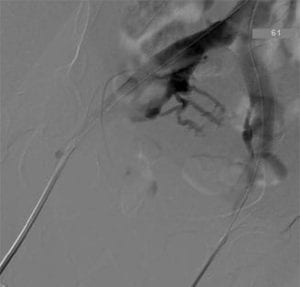

Authors: Back Kim MD, Nay Htyte MD & Tae An Choi, ANP-BC Heart Vein NYC, New York, New York Figure 1. Bilateral deep venous decompression read more